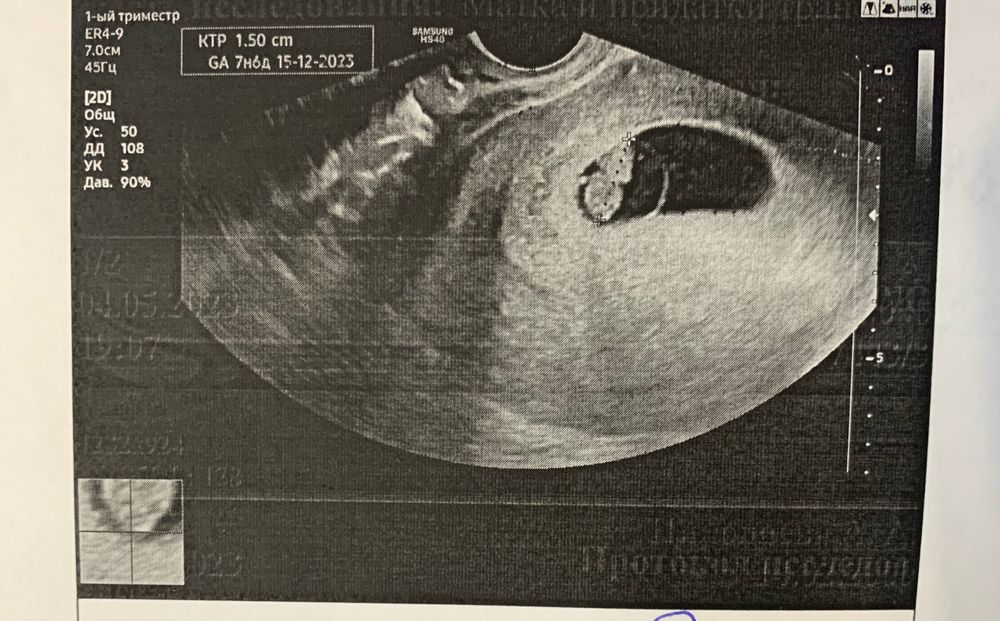

Беременность- 1 триместр ( только до 10 недель)Была сегодня на узи. Врач увидела какое то кистозное образование в голове, это дословно. Быстро все свернула сказала в 12 недель посмотрим. Сегодня 8 недель. Идем ровно день в день. Понимаю,что рано, но ничего с собой поделать не могу ☹️